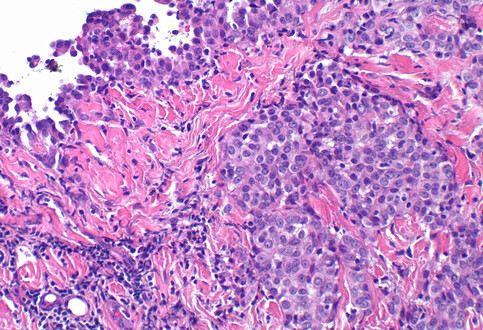

OPTIClear: A Novel Tissue Clearing Agent for the Next Generation Histology

the optical properties of tissue while leaving the structural components unchanged, minimizing tissue damage